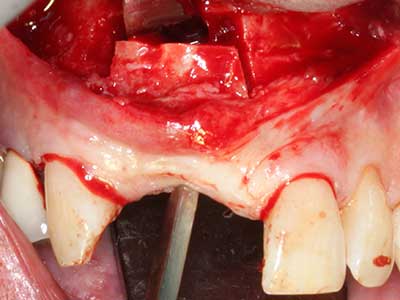

Abb. 21: Ausgedehnter OK-Frontzahndefekt mit Indikation zur Distraktionsosteogenese bei vernarbtem Weichgewebe nach Vor-Operation.

Abb. 22: Das mobile Segment kann präzise mit der dünnen Osteotomiesäge (W&H Piezomed) separiert werden.